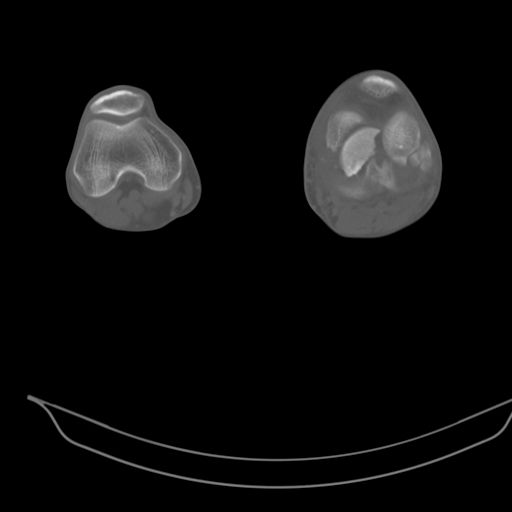

CT shows major bony fragments which are markedly rotated .With this amount of bony damage,you probably should attempt to get reasonably loooking knee with ORIF and thn if he needs a TKR due to pain a few years from now, then tleast you have something looking like a knee that you can replace rather than having to use revision knee for a primary TKR now. 4 weeks is not too long .what is the condition of soft tissues?

При внутрисуcтавных переломах трехмерные (3D) изображения, кроме красивого снимка, не дают полную информацию о состоянии отломков, самыми информативными являются корональные срезы на КТ и обычная длинная ренгенограмма конечности для сравнения оси конечности.

Фронтальные внутрисуставные переломы мыщельков бедра, так называемые Hoffa fracture, не частые, но встречающиеся переломы, в основном они связаны с травмой высокой энергией.